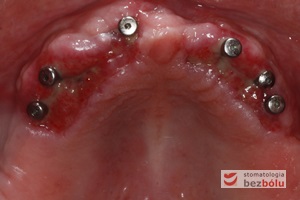

Ekspozycja implantów w szczęce - przesunięcie płata z podniebienia na stronę wargową w celu zwiększenia objętości dziąsła

Ekspozycja implantów w szczęce – przesunięcie płata z podniebienia na stronę wargową w celu zwiększenia objętości dziąsła